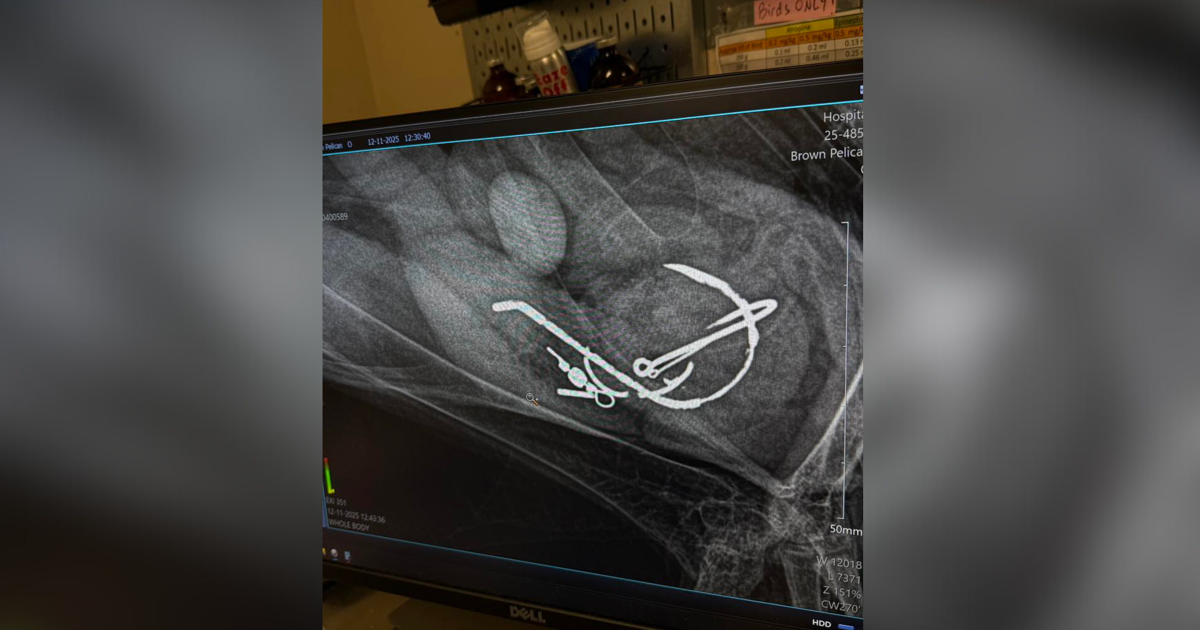

According to a post on CROW’s Facebook page, Dr. Comolli successfully removed five hooks and some fishing line from a pelican’s stomach. The pelican was sedated, and Dr. Comolli used a lubricated glove to carefully retrieve the items.

pelicans swallowed hooks